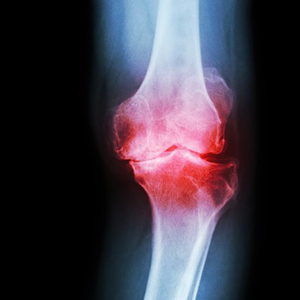

• Bólach stawowych i zwyrodnieniach.

laser therapy on a knee used to treat pain. selective focus